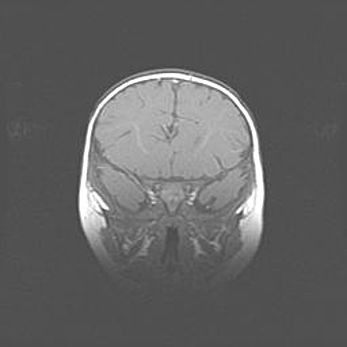

Открытая гидроцефалия.

Возраст: 6 месяцев 15 дней

Вес: 6200 г

Пол: женский

Окружность головы: 41 см

Срок гестации: 38 недель

Гидроцефалия головного мозга у новорожденных – это скопление избыточного количества цереброспинальной жидкости в головном мозге. Ее избыточное скопление в мозге приводит к патологическому расширению желудочков мозга (четырех полостей, расположенных в глубине белого вещества мозга, заполненных цереброспинальной жидкостью и связанных узкими проходами).

Открытый тип гидроцефалии (сообщающаяся) наблюдается тогда, когда нарушен механизм всасывания ликвора в системный кровоток. При этом типе причиной заболевания чаще всего является перенесенные ранее инфекции (например: менингит),  либо же наличие крови в субарахноидальном пространстве.